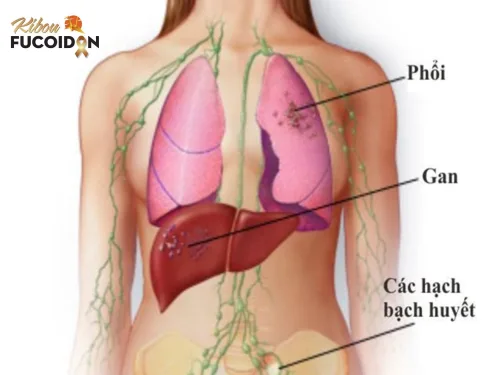

Dấu hiệu cảnh báo ung thư vú di căn phổi và cách điều trị

Ung thư vú di căn phổi là giai đoạn tiến triển nghiêm trọng của bệnh ung thư vú, khi các tế bào ung thư lan sang phổi và ảnh hưởng ...